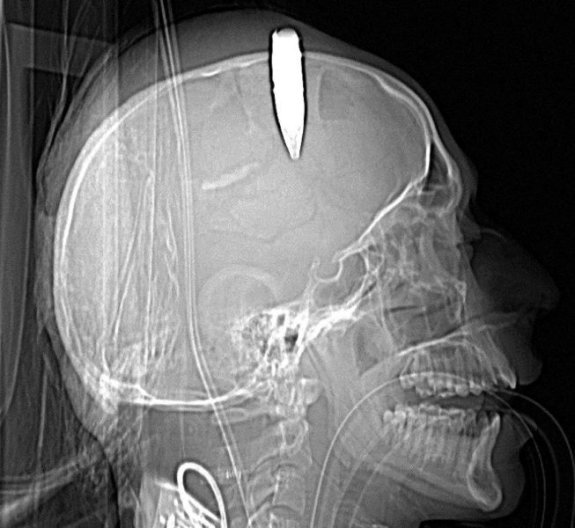

soldier

This X-ray shows a 14.5 millimeter live round of ammunition lodged in the skull of an Afghan soldier. A U.S. military doctor successfully removed the unexploded round -- more than 2 inches long -- at the Bagram Air Field hospital in Afghanistan in the fall of 2014. Notice the life-saving medical tubes placed in his mouth and throat.